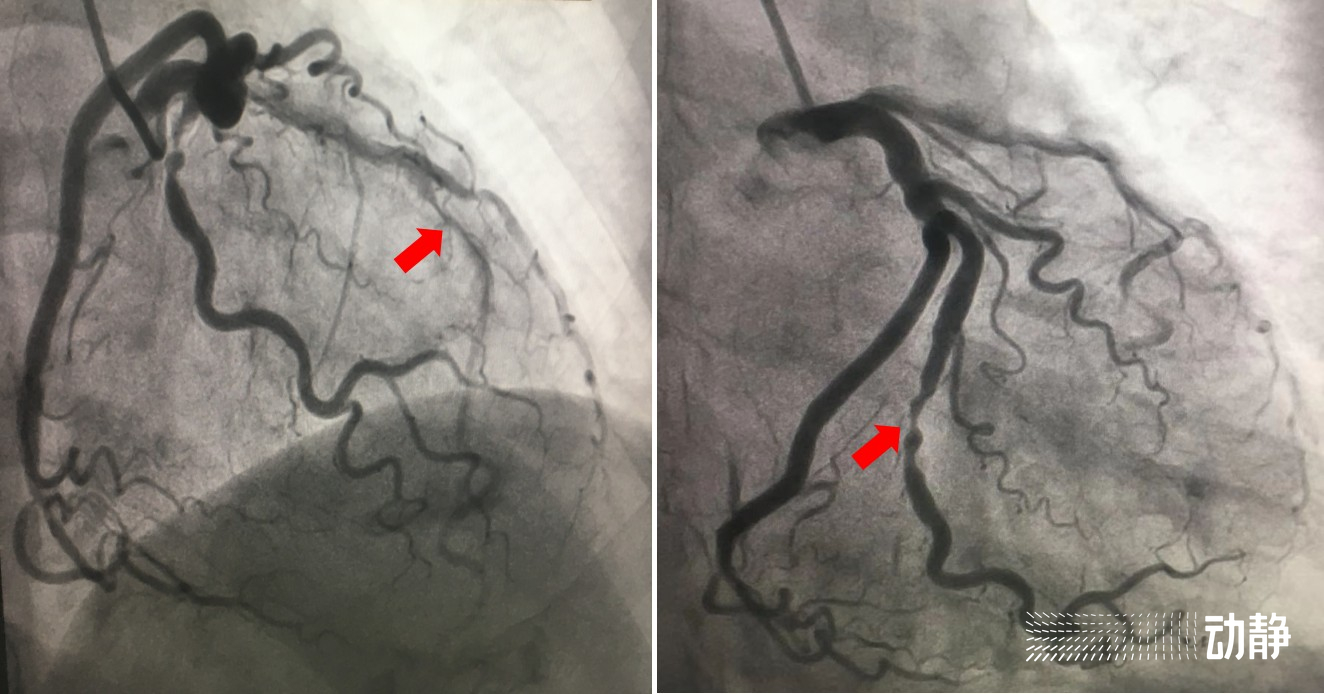

在专家团队的默契配合下,仅1小时左右,就成功同时在夏婆婆的前降支血管及回旋支血管各植入1枚支架。陈游洲说:“对于夏婆婆这个病例来说,我们的手术大大节约了时间。考虑到她的身体条件,我们采用了恰当的造影剂用量,支架尺寸准确,医生操作准确,都为缩短手术时间、减轻患者痛苦做出了贡献。”